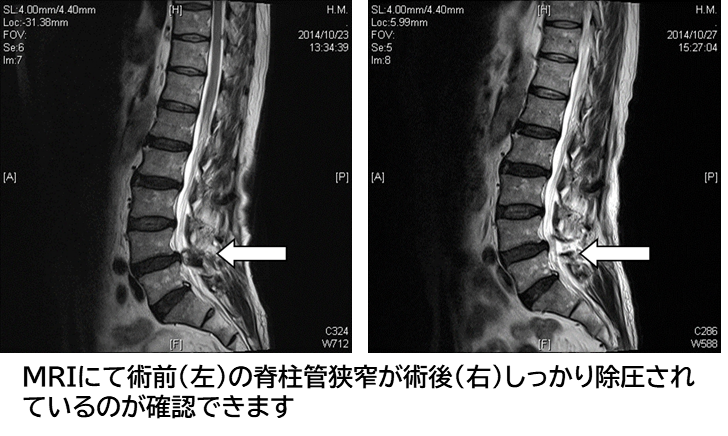

腰部脊柱管狭窄症に対しては従来、棘突起切除もしくは棘突起縦割した後に椎弓切除、黄色靱帯切除することで狭窄した脊柱管を拡大し、脊髄を除圧しておりましたが、約16mmの円筒を使用してできるだけ低侵襲に脊髄を除圧することで早期社会復帰を目標としております。

当院では入院期間が約3日間です。